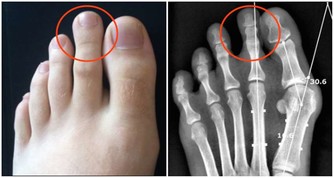

晚上睡覺時,身體一旦出現這4種變化,說明你的尿酸已“超標”!

在生活中有兩種現象,一種是有人在痛風發作後,才知道自己的血尿酸水平已經遠超正常值;另一種現像是,在體檢時發現自己尿酸值高,但是,沒有什麼自覺症狀。

眾所周知,一旦尿酸高了,會引發全身性疾病,首當其衝的就是關節疾病,對於腎臟、血管等都會有不同程度的損害,還會影響血糖引發糖尿病等等。

如果尿酸高了,晚上睡覺時身體會出現下面幾種情況,千萬不要忽視!